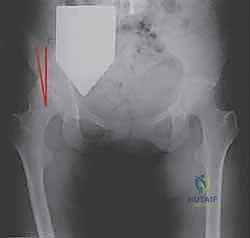

Radiographic parameters indicating surgery typically include a lateral center-edge angle of Wiberg less than 20 degrees, an anterior center-edge angle less than 20 degrees, and an acetabular index (Tönnis angle) greater than 10 degrees. Crucially, the hip must demonstrate congruency on functional radiographs (abduction and internal rotation views) and possess preserved articular cartilage (Tönnis grade 0 or 1).

Thorough preoperative planning is non-negotiable. Standard radiographic evaluation includes a weight-bearing anteroposterior pelvis, a false profile view of Lequesne and de Sèze to assess anterior coverage, and a Dunn or cross-table lateral view to evaluate for concurrent cam morphology. The von Rosen view (abduction and internal rotation) is critical to confirm that the femoral head can be concentrically reduced into the dysplastic acetabulum once reoriented.

Fluoroscopy confirms the correction, ensuring a normalized lateral center-edge angle, horizontal Tönnis roof, and appropriate anterior coverage without inducing retroversion (which could cause iatrogenic femoroacetabular impingement). Fixation is achieved using three or four fully threaded 3.5mm or 4.5mm cortical screws directed from the intact ilium into the mobilized fragment.